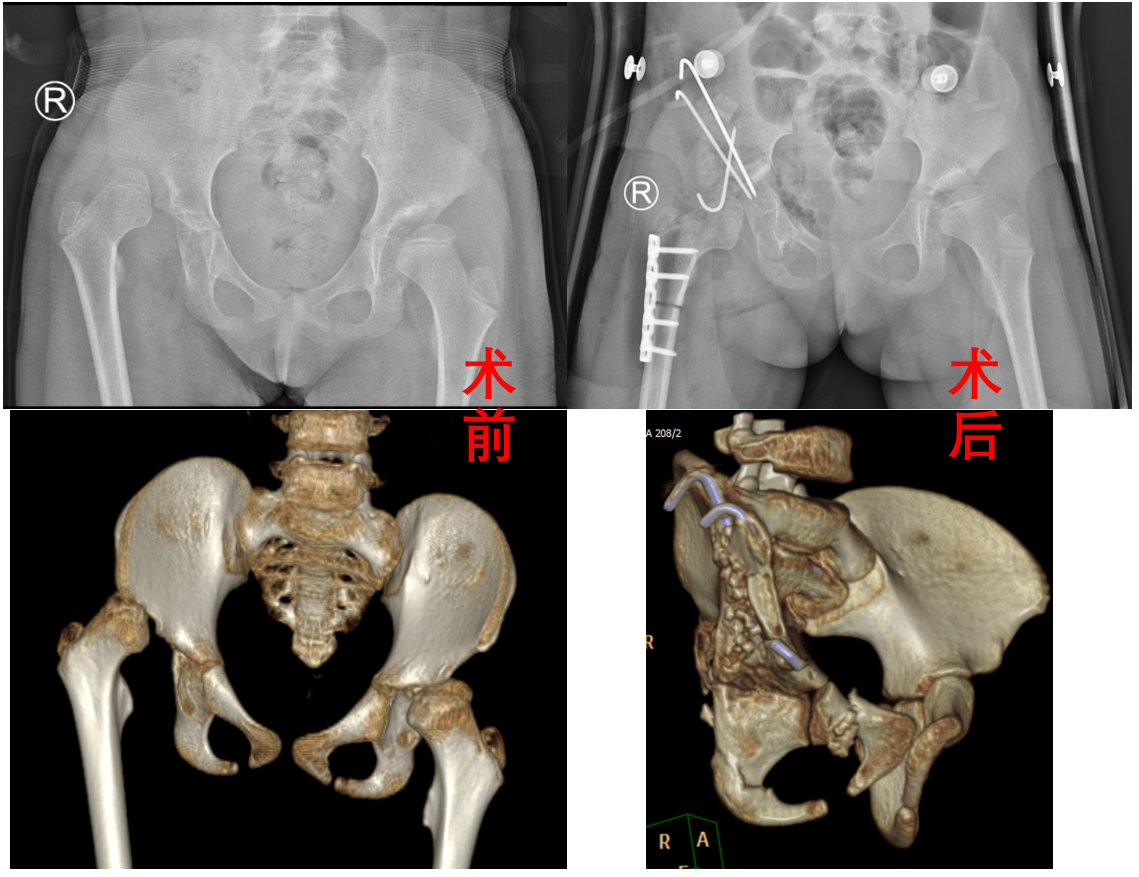

患儿7岁2月,入院前5年初学走路时发现跛行症状,家属未充分重视,跛行步态随生长逐渐加重,直至入院前2月确诊为右侧DDH,经多方求医后就诊于兰大二院。入院后,小儿骨科任小军副主任医师在刘文忠主任指导下,充分评估患儿病情,开展病例讨论、集体讨论,最终确定实施Bernese骨盆三联截骨术,并联合实施股骨近端短缩去旋转截骨内固定术。术后效果良好,术后1周后康复出院。

发育性髋关节发育不良(DDH)是小儿骨科最为常见的髋部畸形,早诊断、早治疗可终生获益,但目前仍有部分患儿无法及时的开展早期诊断和正确治疗,导致晚期确诊时已失去最佳治疗时机,遗留关节畸形、疼痛和功能障碍,导致患儿出现终生残疾。Bernese骨盆截骨术是目前国内外治疗DDH最新、操作最复杂的手术方式,手术时截骨线靠近髋臼,可以使髋臼获得最大程度旋转,增加股骨头覆盖,髋关节旋转中心更接近正常关节,最符合正常生物力学要求,在治疗大龄DDH患儿方面临床效果显著。